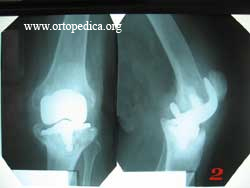

2. Компрессионный перелом кости

4. Посттравматический вывих эндопротезированого коленного сустава через 4 года после первичной операции